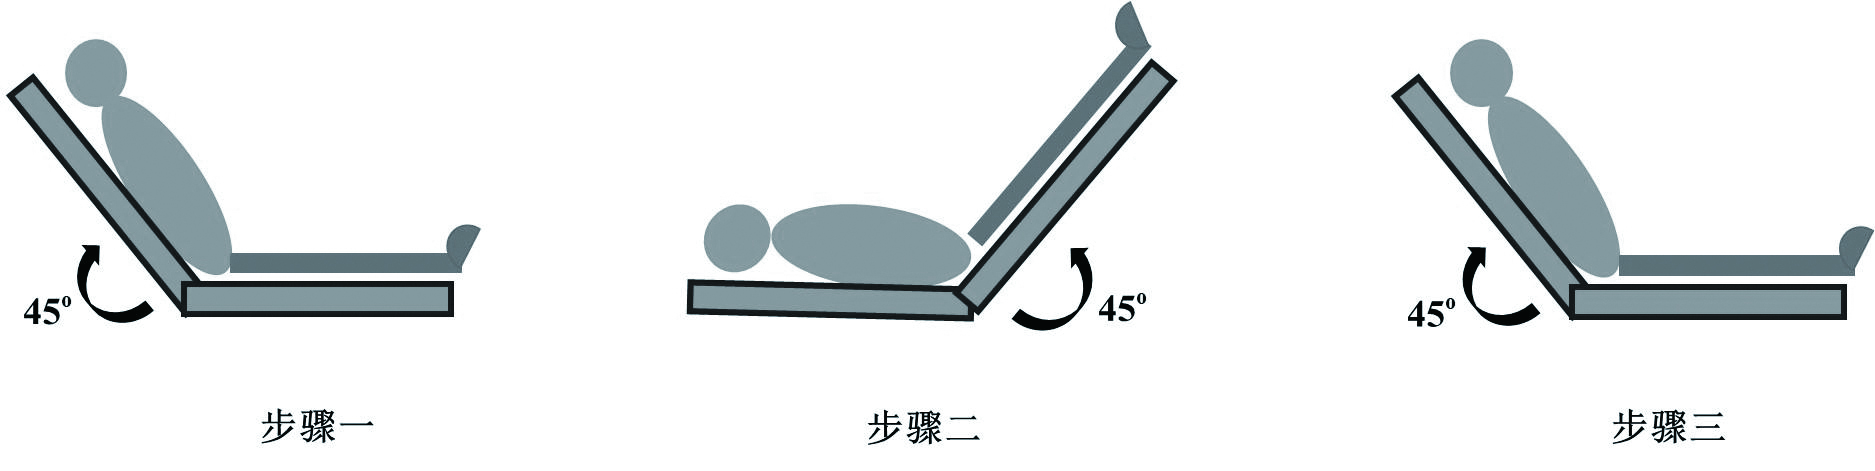

(1)半卧位抬高45°维持2 min,用超声测得CO指标,作为基线数值;(2)取仰卧位,下肢抬高45°维持1 min,用超声记录CO指标;(3)取步骤一体位,维持2 min,测量超声CO数值,评估CO指标是否回至基线数值[8]。见图 2。

|

| 图 2 PLR试验操作步骤 Figure 2 The procedure of passive leg raising test |

|

|